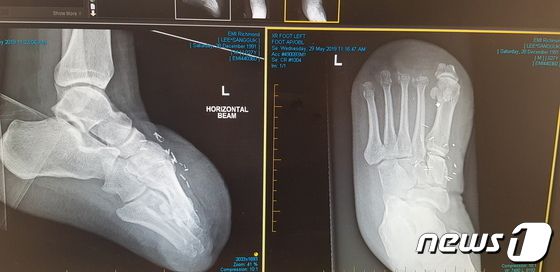

이상국씨 발가락 절단 엑스레이 사진(이상국씨 제공) ⓒ 뉴스1 |

이씨가 탄 선박은 호주 멜버른항으로 이동·정박해 메인엔진 크로스헤드 베어링 결함 수리를 진행했다. 이 과정에서 2019년 3월12일 선박 내 체인블럭이 파손되면서 약 40m가량 공중으로 들어 올려져 있던 6톤 무게의 부품(크로스헤드 핀)이 이씨의 발등 위로 떨어져 발가락 10개가 모두 절단됐다. 취업한 지 26일 만이다.

사고 직후 이씨는 발가락을 접합할 수 있는 골든타임을 놓친 채 호주 병원으로 이송, 현재까지 홀로 현지에서 재활치료를 받고 있다.